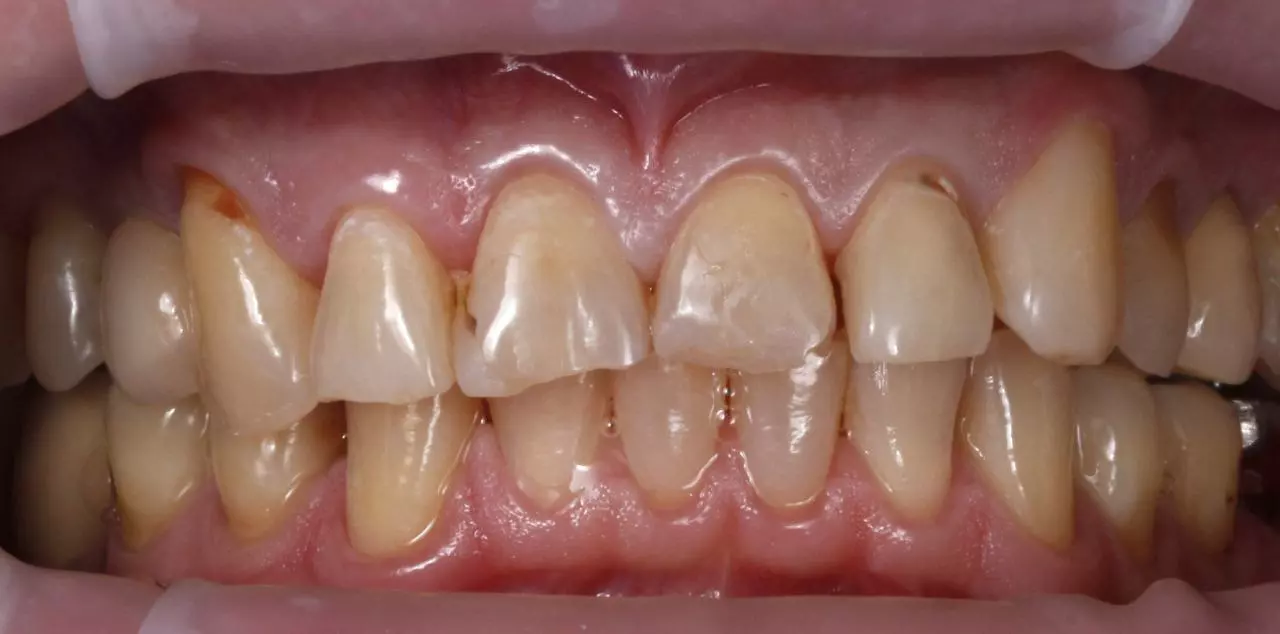

Художня реставрація 13.12.11.21.22.